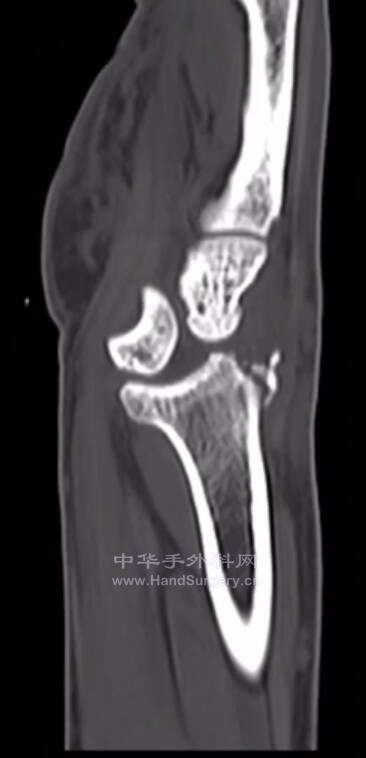

这是月骨脱位还是月骨周围脱位?